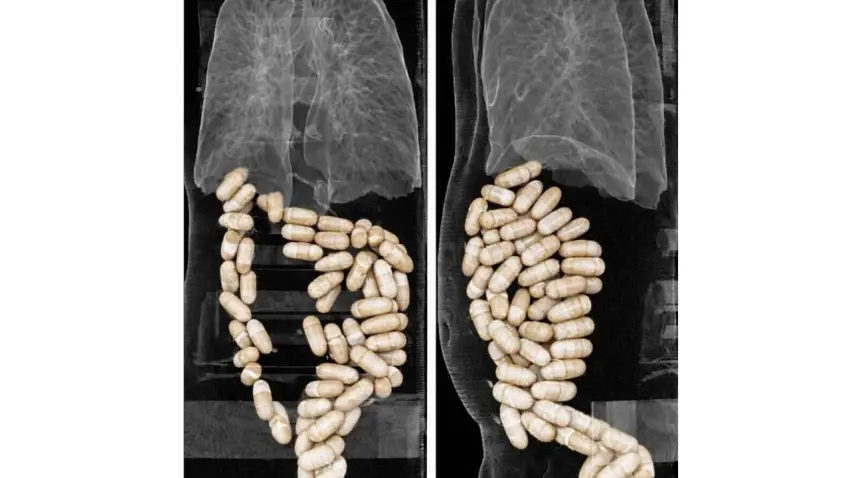

Midelerinden 1 kilo 304 gram uyuşturucu madde çıktı

İzmir'de, havalimanında gözaltına alınan 2 şüphelinin midesinden 127 kapsül halinde toplam 1 kilo 304 gram uyuşturucu çıktı. Şüpheliler çıkarıldıkları mahkemede tutuklandı.

Midelerinden 1 kilo 304 gram uyuşturucu madde çıktı haberinin görseli

Narkotik Suçlarla Mücadele Şube Müdürlüğü ekipleri, istihbarat çalışmasıyla yurt dışından 2 şüphelinin kapsül halindeki uyuşturucu maddeyi yutarak Türkiye'ye getirecekleri bilgisine ulaştı. Ekipler, bunun üzerine önceki gün, İzmir Adnan Menderes Havalimanı'nda önlem aldı. Hastaneye sevk edilen E.E. ve N.M.'nin yapılan radyolojik görüntülemelerinde, midelerinde toplam 127 kapsül halinde toplam 1 kilo 304 gram eroin olduğu ortaya çıktı. Midelerindeki kapsüller İzmir Katip Çelebi Üniversitesi (İKÇÜ) Atatürk Eğitim ve Araştırma Hastanesi'nde doğal yollarla çıkartılan E.E. ve N.M., sevk edildikleri adliyede çıkarıldıkları mahkemede tutuklandı.şüheliler